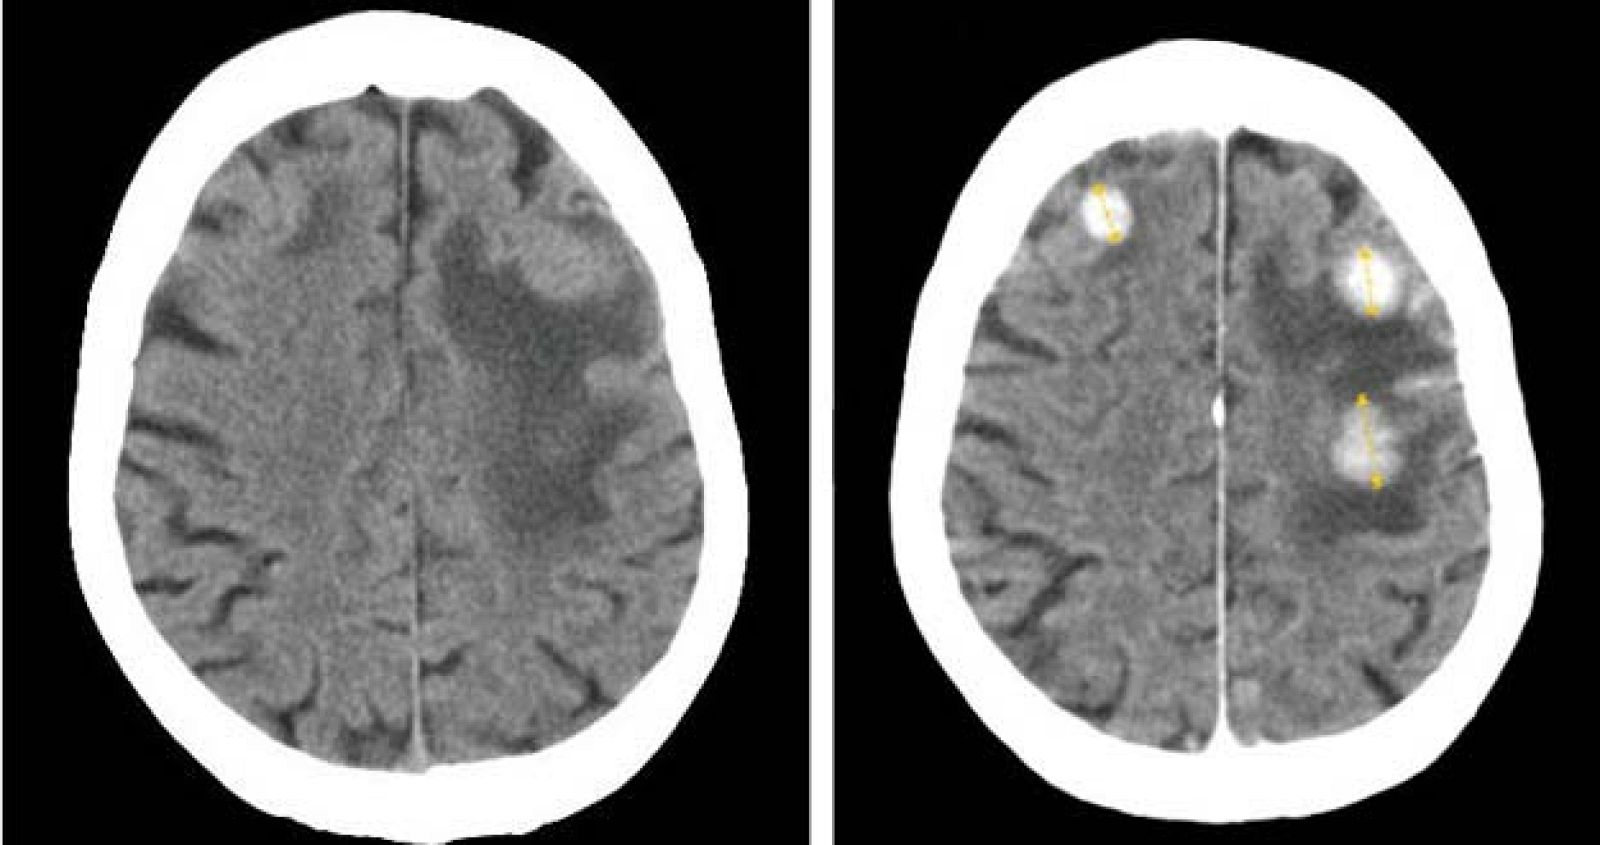

Tomografía computarizada de tres metástasis cerebrales